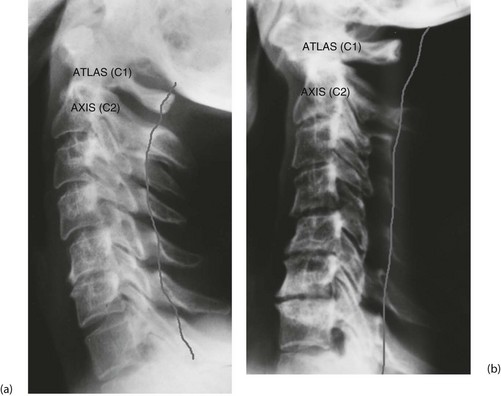

• Odontoid subluxation (Fig. 8.7)—if rheumatoid arthritis involves the atlanto-axial joint, the transverse ligament may be destroyed, allowing the odontoid process to sublux. During general anaesthesia, the protective reflexes are lost. If the neck is hyperextended during intubation, there is a serious risk of injury to the spinal cord by the unrestrained odontoid

Full blood count is essential to check for non-specific anaemia or iron deficiency anaemia; and plasma urea, electrolytes and creatinine are measured to identify chronic or drug-induced disturbance of renal function; inflammatory markers (ESR and CRP) indicate the activity of the disease. Preoperative assessment must include clinical examination of neck movements and cervical spine X-rays.